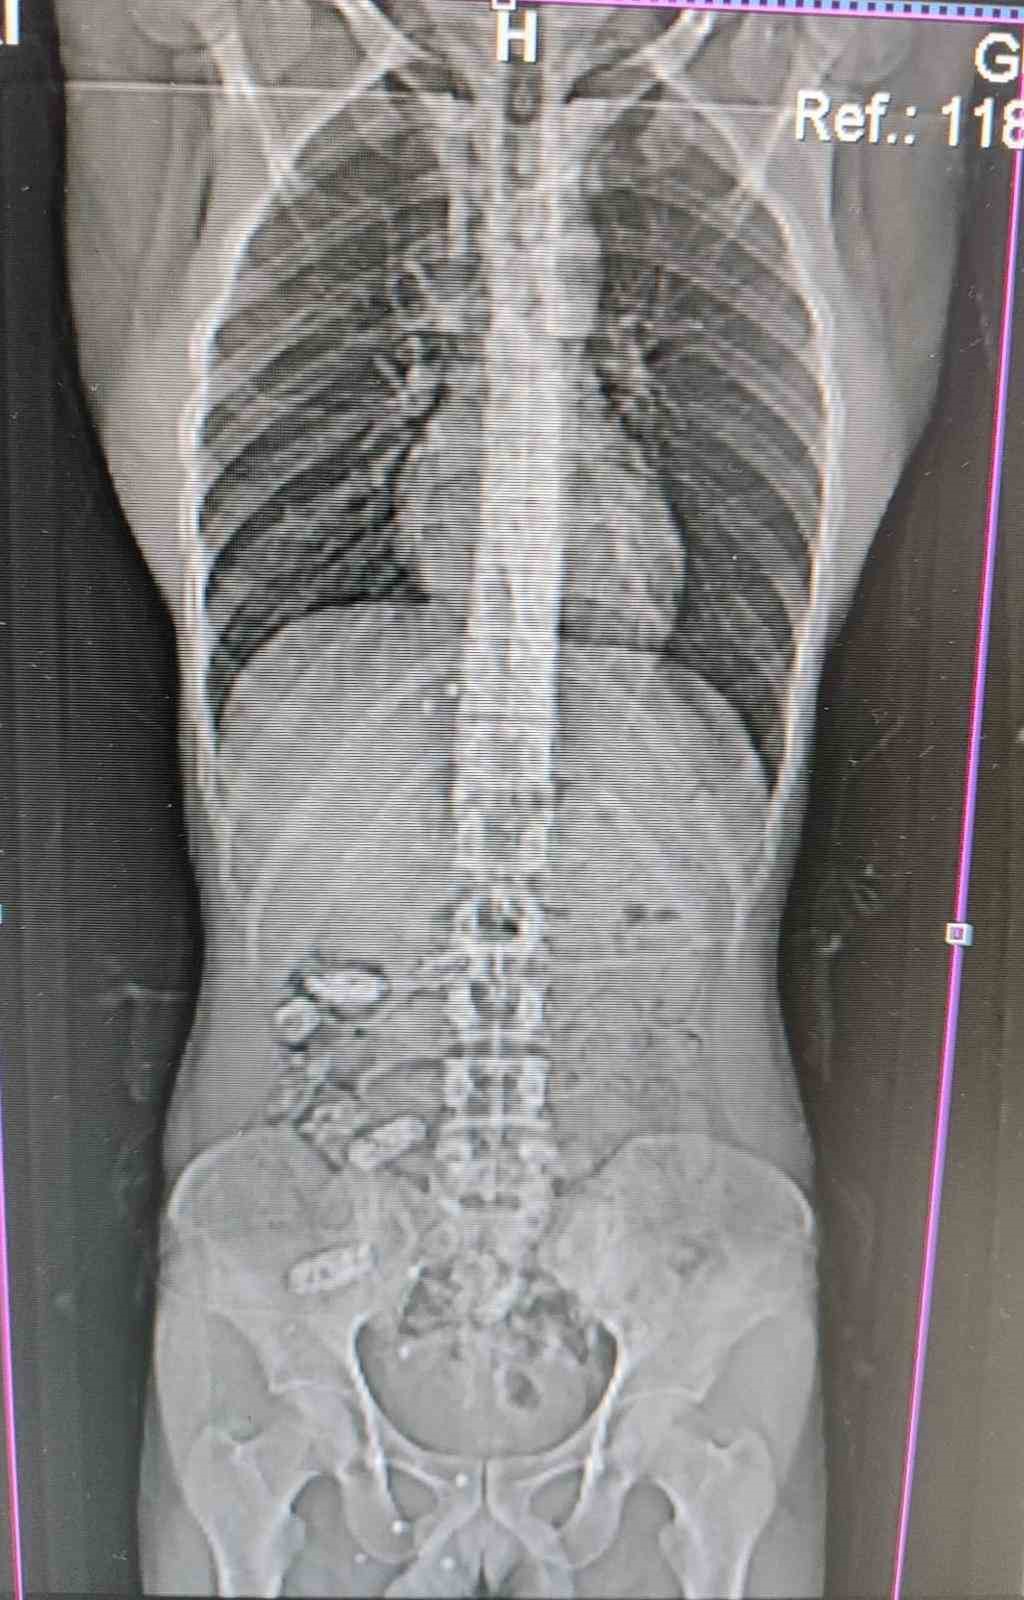

Uyuşturucu kuryesinin midesinden 18 kapsül çıktı

Gümüşhane’de polis ekiplerinin kontrol noktasında durdurduğu araç içerisindeki yabancı şahsın midesinden 18 adet kapsül halinde metamfetamin ele geçirildi. Edinilen bilgilere göre, Gümüşhane İl Emniyet Müdürlüğü’ne bağlı Narkotik Suçlarla Mücadele Şube Müdürlüğü ekipleri tarafından Akçakale Uygulama Noktası’nda durdurulan bir araç içerisindeki yabancı şahsın şüpheli hareketleri üzerine çalışma yapıldı. Uyuşturucu kuryesi olduğu ve yutma suretiyle uyuşturucu taşıdığından şüphelenilen şahsın Gümüşhane Devlet Hastanesi’nde yapılan kontrollerinde, midesinde 18 adet kapsül olduğu tespit edildi. Hastanede yapılan müdahalenin ardından şahsın midesinden çıkarılan kapsüllerin içerisinde toplamda 152,29 gram metamfetamin ele geçirildi. Hakkında Uyuşturucu Madde İmal ve Ticareti suçundan işlem başlatılan yabancı uyruklu şahıs yasal işlemlerinin tamamlanmasının ardından çıkarıldığı mahkemece tutuklanarak cezaevine gönderildi.